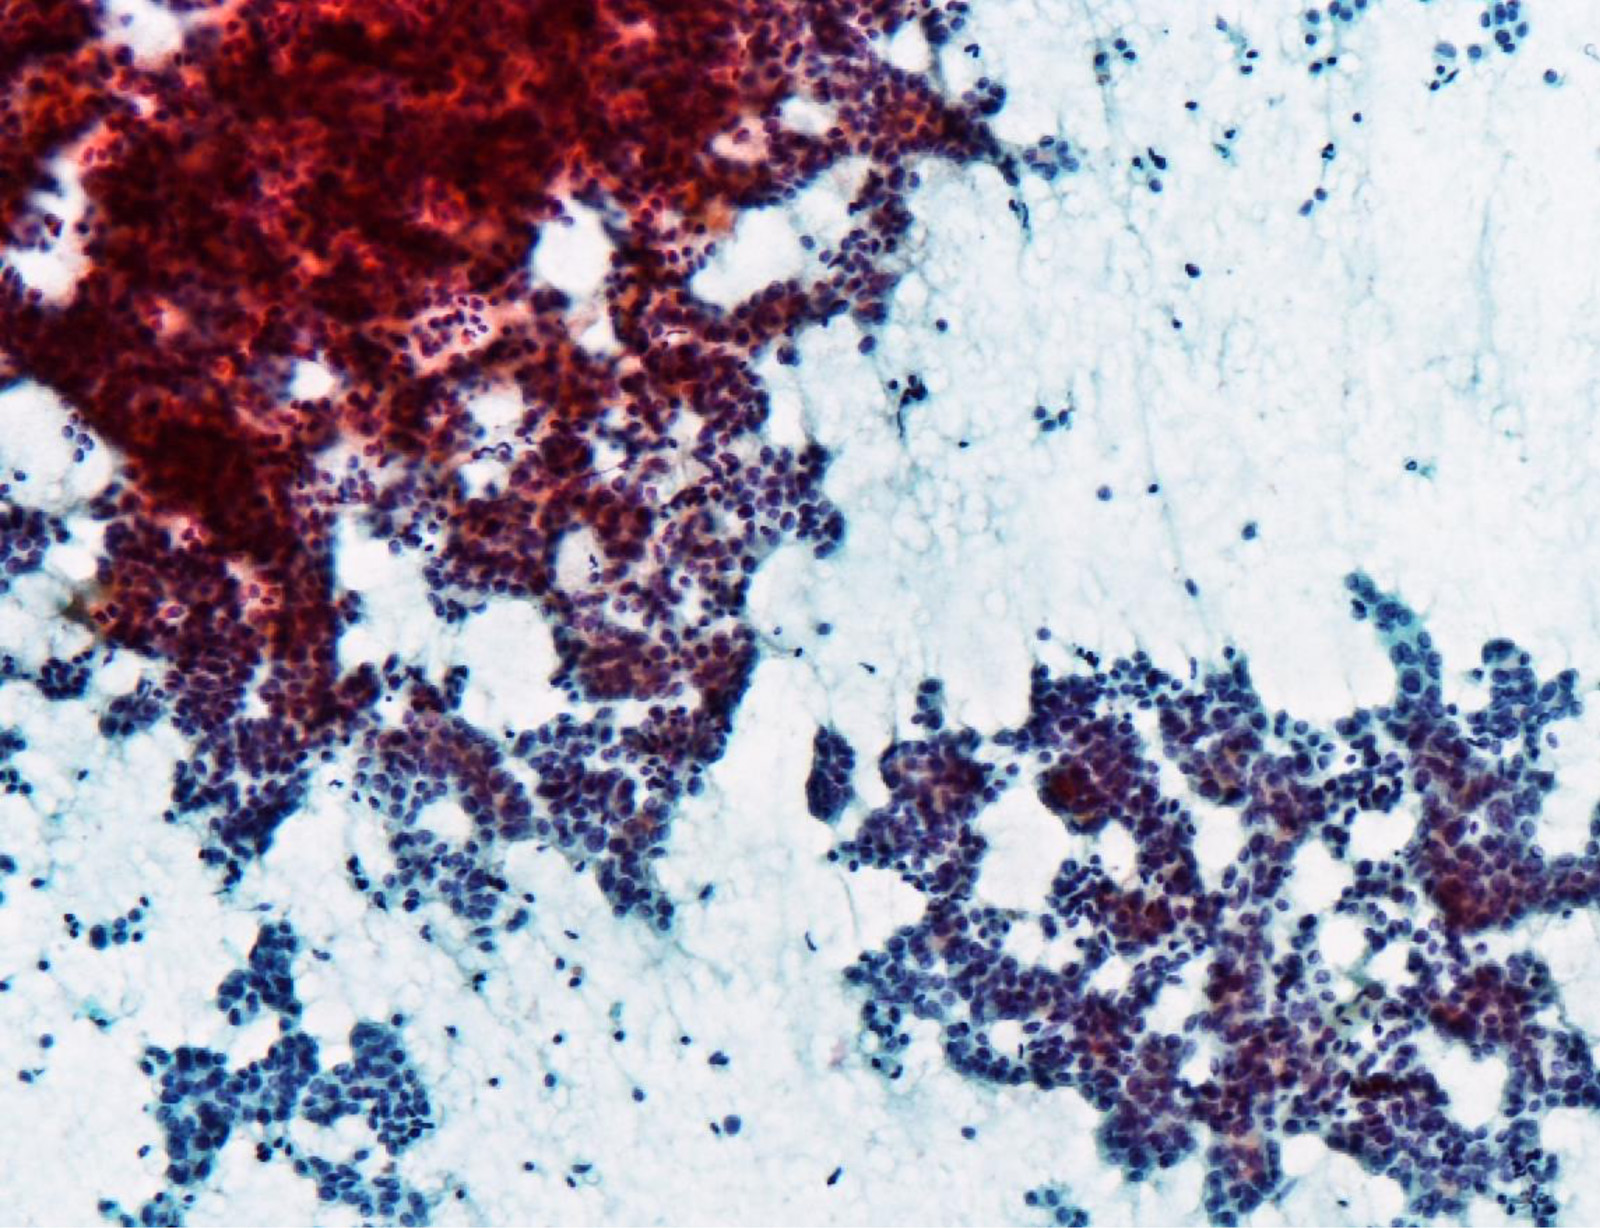

Cytology description

- Hypercellularity

- Small, round and dense colloid (hyaline colloid) may be present, sometimes within follicles

- Cells arranged in microfollicles or trabecular pattern

- Nuclear enlargement but may lack prominent nuclear features of papillary carcinoma (Am J Clin Pathol 1999;111:216)

- Highly suggestive of syncytial clusters, microfollicular architecture, chromatin clearing and nuclear grooves (Acta Cytol 2006;50:663)

- Classified by Bethesda system as categories III to VI

- Cytologically unable to distinguish between noninvasive and invasive

Cytology images

Contributed by Ayana Suzuki, C. T.